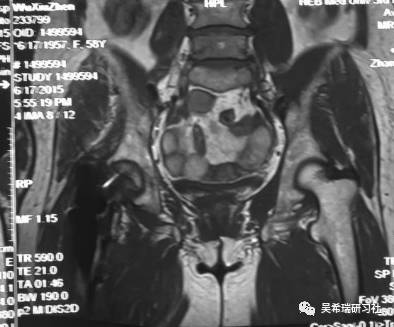

双下肢车祸外伤保肢的理由是足底皮肤好

TIPS:清创&盐水冲洗(不用双氧水)VSD骨水泥技术&开放植骨单边外固定架(下胫腓联合固定)早期下地 生理应力 + 机械应力游离植皮 / 不用皮瓣清创时游离皮质骨去除胫跖骨牵引技术防治&纠正足下垂